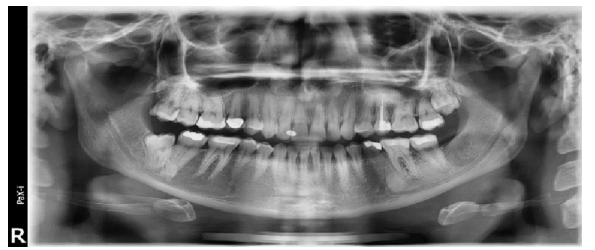

Figll Demonstrating in right side an integrated pattern of classification

(Distoangular impaction according to winter and class 3 position B according to Bell and Gregorys classification)

Impactions seen in fig. 11 are a good example of integrated pattern, reporting the type of impaction with this pattern give good estimation to the operator warn against complications like jaw bone fracture due to mass bone removal in all direction. This will help the operator to have preparedness for such mishaps and, warn the patient and get his consent for such an expected complication